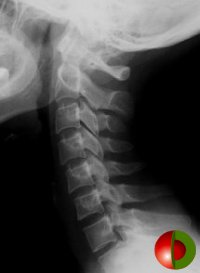

C Spine

Click on image (To learn how to assess C-spine Xrays)

Atlas dens interval (ADI) - < 3 mm adult < 5 mm child

Wackenheim line - extension back of clivus, within 1 to 2mm of dens tip

Spinolaminar line C1 to C3 - within 2 mm

Space available for cord (SAC) - > 13mm adults